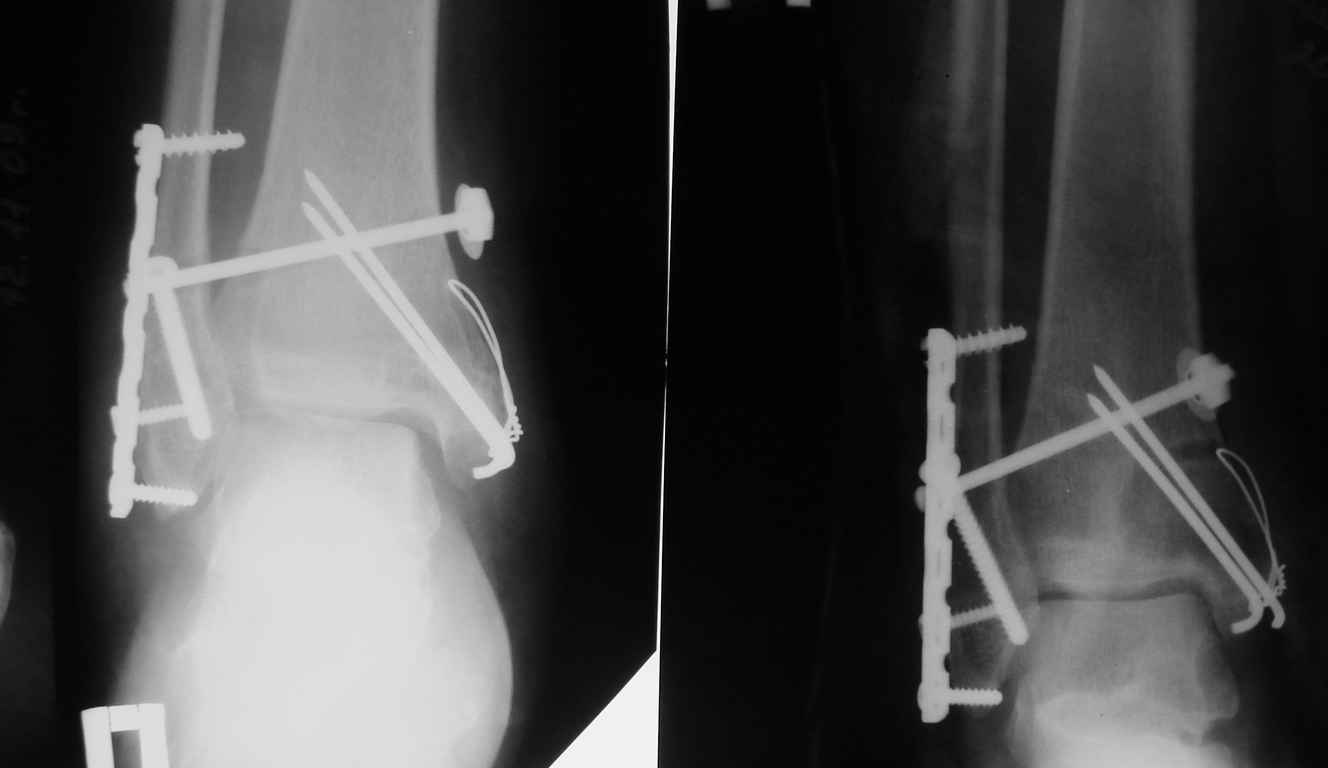

Случай прошлого года:пациентка-молодая, крупная женщина, 30лет. Травма в начале апреля

2009г-пронационный перелом лодыжек с подвывихом стопы.Ко мне обратилась через 35

дней,прооперирована 22.05.2009г.Внутренняя лодыжка фиксирована по Веберу,наружная

реконструктивной пластиной с наложением болта-стяжки.Иммобилизация "сапожок" в течении

месяца,затем пригипсовано "стремя".Гипс снят 10.07.2009г

Достаточно быстрое восстановление функции. В октябре 2009г -

почувствовала боль, в области рубца над гайкой открылся свищ. На

Р-граммах-консолидация переломов и смещение гайки по стяжке.

10.11.2009г-конструкции удалены, санация, заживление ран. В настоящее

время пациентку ничего не беспокоит. На операции - раскручивание гайки

- болталась на конце стяжки.

шайбу-гровер? Тщательно моделировать пластину?Прилагаю сравнительные

снимки - сразу после операции и перед удалением конструкции.